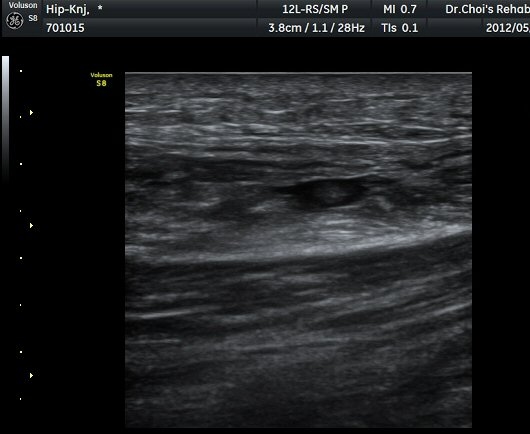

ÀüÇÏÀå°ñ±Ø(AIIS) Ⱦ´Ü¸é °Ë»ç»ó ÀüÇÏÀå°ñ±Ø°ú µÇÅðÁ÷±ÙÀÇ ÈûÁÙÀÌ °üÂûµÈ´Ù(±×¸² 1).

ŽÃËÀÚ¸¦ ¾Æ·¡·Î À̵¿ÇÏ´Ï ´ëÅðÁ÷±Ù³»¿¡ Àú¿¡ÄÚ º¯º¯ÀÌ °üÂûµÈ´Ù(±×¸² 2, 3).